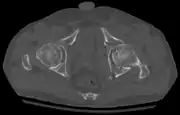

X-ray visualization is best done in Antero posterior view and Iliac and obturator oblique views. In CT scan the characteristic feature is that the fracture line runs from front to back. CT scan also helps in identifying impaction of bone pieces and if there are pieces in the joint

To understand the fracture pattern of a fractured acetabulum, it is essential to have minimum three x-ray views, though use of CT scan with 3-D reconstruction of images has made understanding of these fractures easier.

In all cases, CT scan can assist in identifying impacted bone pieces, which may be found within the joint, and MRI may be done to identify the extent of potential injury to the sciatic nerve.